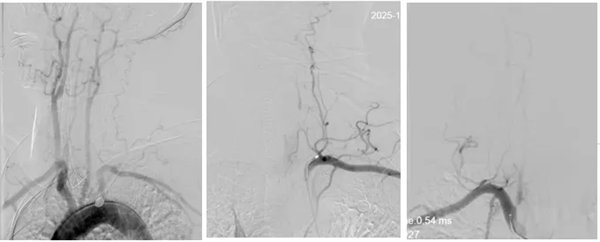

為最大程度搶救腦細胞,縮短腦組織供血恢復間隔,神經內三科卒中救治團隊立即啟動綠色通道實施介入取栓治療,麻醉醫師迅速抵達導管室,神經內三科主任席聰對患者進行急診血管造影后發現:患者左椎動脈起始段閉塞,右椎動脈起始部次全閉塞。

術中,介入團隊精準定位血管閉塞部位,通過微導絲“探路”聯合球囊擴張技術開通右側椎動脈開口,造影椎開口殘余狹窄60%?;讋用}血栓形成,基底動脈管腔狹窄55%,基底動脈尖堵塞,右側大腦后動脈及小腦上動脈未見顯影,左側大腦后動脈P3以遠閉塞。